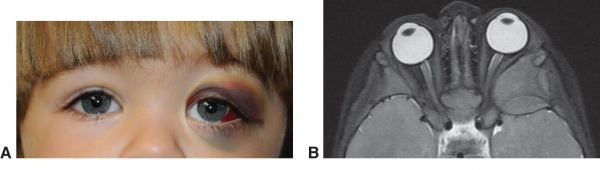

The most common clinical presentation of orbital neuroblastoma metastases in patients less than two years old is unilateral or bilateral periorbital or eyelid ecchymosis, typically called “raccoon eyes” (Figure 1).[26] This can often be confused for traumatic injury (mainly non-accidental) because of the deposition of blood in the eyelids. Less common clinical findings include proptosis,[27] periorbital swelling,[28] periorbital hemorrhage,[29] strabismus, restricted ocular motility,[30] ipsilateral Horner syndrome[31], ptosis,[32] iris heterochromia, opsoclonus/ myoclonus syndrome,[33] convergent strabismus, optic nerve atrophy or edema, and blindness.[34]

Figure 1a. "Raccoon Eyes" upon presentation

Figure 1b. After chemotherapy

A Horner’s syndrome (miotic pupil, ptotic eyelid, and anhidrosis) may result from a primary thoracic neuroblastoma involving the sympathetic chain[31]. Iris heterochromia is typically caused by congenital neuroblastoma of the cervical ganglion resulting in Horner’s. A recent study by Shabat et al, showed that from 135 patients newly diagnosed with neuroblastoma, none of those was it related with Horner's syndrome. Only one patient who had Horner syndrome the tumor had been identified prenatally and confirmed by imaging postnatally. They concluded that, Horner syndrome may not be as correlated as previously thought and that in pediatric patients, the "full investigation" could be considered in only patients with other systemic signs and symptoms.[35]